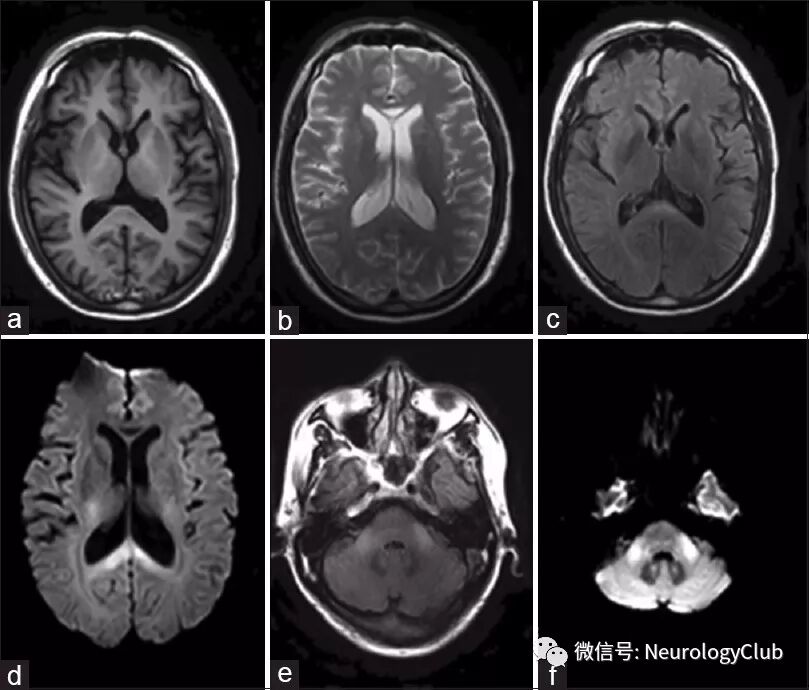

MRI可见双侧小脑中脚及胼胝体异常信号。实验室检查提示谷丙转氨酶95.2U/L,谷草转氨酶96.0U/L。余常规化验正常。未行腰穿及肝脏超声。

(图:a:T1WI可见胼胝体压部低信号;b:T2WI可见胼胝体膝部高信号;c:FLAIR可见胼胝体压部高信号;d:DWI可见胼胝体压部高信号;e:FLAIR可见双侧小脑中脚高信号;f:DWI可见双侧小脑中脚高信号